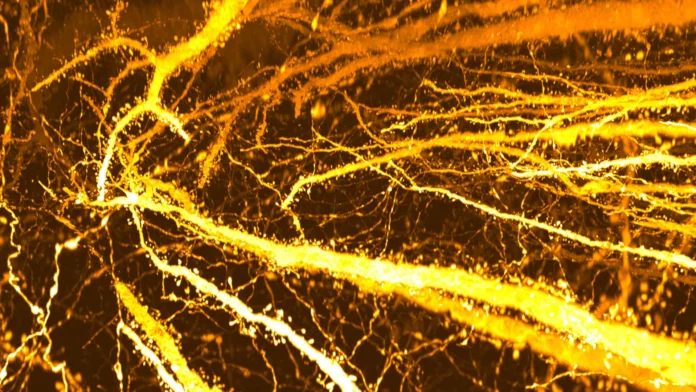

“We did not set out to study brain disorders,” says Professor Takeshi Imai at Kyushu University’s Faculty of Medical Sciences. “After developing a high-resolution tool for synaptic analysis in 2016, we looked at the mouse cerebral cortex out of curiosity. Beyond seeing the beauty of the neuronal structure, we were surprised to discover a previously unknown high-density hotspot of dendritic spines, the tiny protrusions in dendrites where excitatory synapses are formed.”

To study these cells in detail, the team used SeeDB2 — the tissue clearing agent Imai’s team developed — along with super-resolution microscopy. This combination allowed the researchers to examine transparent brain tissue and map dendritic spines across entire Layer 5 neurons for the first time.

The detailed mapping revealed an unexpected pattern. One specific section of the dendrite contained an unusually dense concentration of dendritic spines, forming what the researchers call a “hotspot.” Further analysis showed that this hotspot does not exist early in life and instead emerges during adolescence.

To pinpoint when this change occurs, the team tracked spine distribution across multiple stages of development. In two-week-old mice, before weaning, dendritic spines were spread relatively evenly across the neuron. Between three and eight weeks of age, a period that spans early childhood to adolescence, spine density increased sharply in a single region of the apical dendrite. Over time, this localized growth resulted in the formation of a dense synapse hotspot.